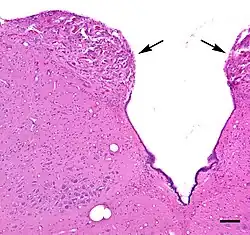

The area postrema is a paired protuberance found at the inferoposterior limit of the fourth ventricle.[1][5] Specialized ependymal cells are found within the area postrema. These cells differ slightly from the majority of ependymal cells (ependymocytes), forming a unicellular epithelial lining of the ventricles and central canal. The area postrema is separated from the vagal trigone by the funiculus separans, a thin semitransparent ridge.[1][5] The vagal trigone overlies the dorsal vagal nucleus and is situated on the caudal end of the rhomboid fossa or 'floor' of the fourth ventricle. The area postrema is situated just before the obex, the inferior apex of the caudal ventricular floor. Both the funiculus separans and area postrema have a similar thick ependyma-containing tanycyte covering. Ependyma and tanycytes can participate in the transport of neurochemicals into and out of the cerebrospinal fluid from its cells or adjacent neurons, glia or vessels. Ependyma and tanycytes may also participate in chemoreception.[1][5]

The area postrema is considered a circumventricular organ because of its proximity to the ventricular system.[2] In a morphological study, area postrema capillaries in the ventral subregion of area postrema were shown to be relatively impermeable like those of the brain, whereas medial and dorsal area postrema capillaries had microscopic characteristics of high permeability, a characteristic called sinusoidal.[6] Subregional capillary density of the area postrema was highest near the ventricular interface, and was nearly twice as dense as the capillary densities of the adjacent solitary nucleus (SN), and dorsal motor nucleus of the vagus nerve.[6] A tanycyte barrier partially compensates for high capillary permeability in the area postrema.[7]